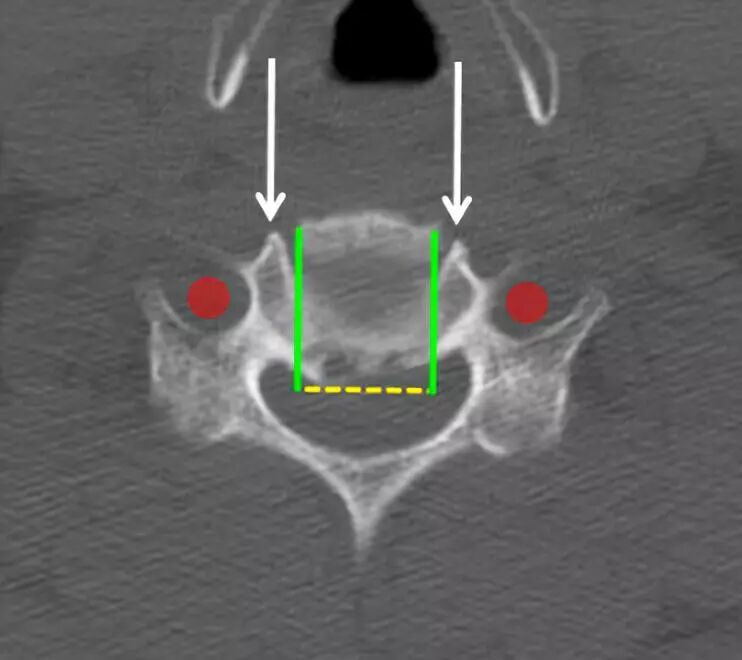

用咬骨钳和刮匙除去椎间盘组织。

注意保持在横向的钩突关节(白色箭头)的边缘内。椎动脉(红色圆圈)位于其侧面外侧。

分离后纵韧带并切除。

可以在头端和尾端椎体后面轻轻地穿过神经探钩以确认脊髓减压充分。然后神经钩可以从椎间孔中穿出以确认神经根减压。